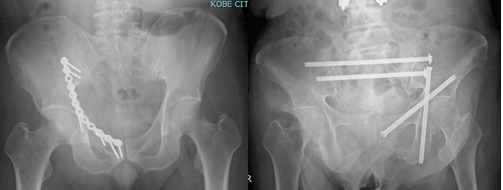

当センターは、救急救命センターを有する基幹病院の整形外科部門として、四肢・骨盤外傷に対する高度急性期医療と再建医療を担っています。高エネルギー外傷、多発外傷、開放骨折、骨盤骨折などの重度外傷を含む幅広い症例に対応し、迅速かつ的確な診断・治療を行っています。さらに、急性期治療にとどまらず、偽関節、変形治癒、骨欠損、重度軟部組織損傷に対する再建医療まで一貫した専門診療を行い、患肢機能の温存・再建と早期の社会復帰を見据えた質の高い医療を提供します。

診療実績はこちら- 骨盤輪・寛骨臼骨折

学会発表・論文はこちら骨盤・寛骨臼骨折